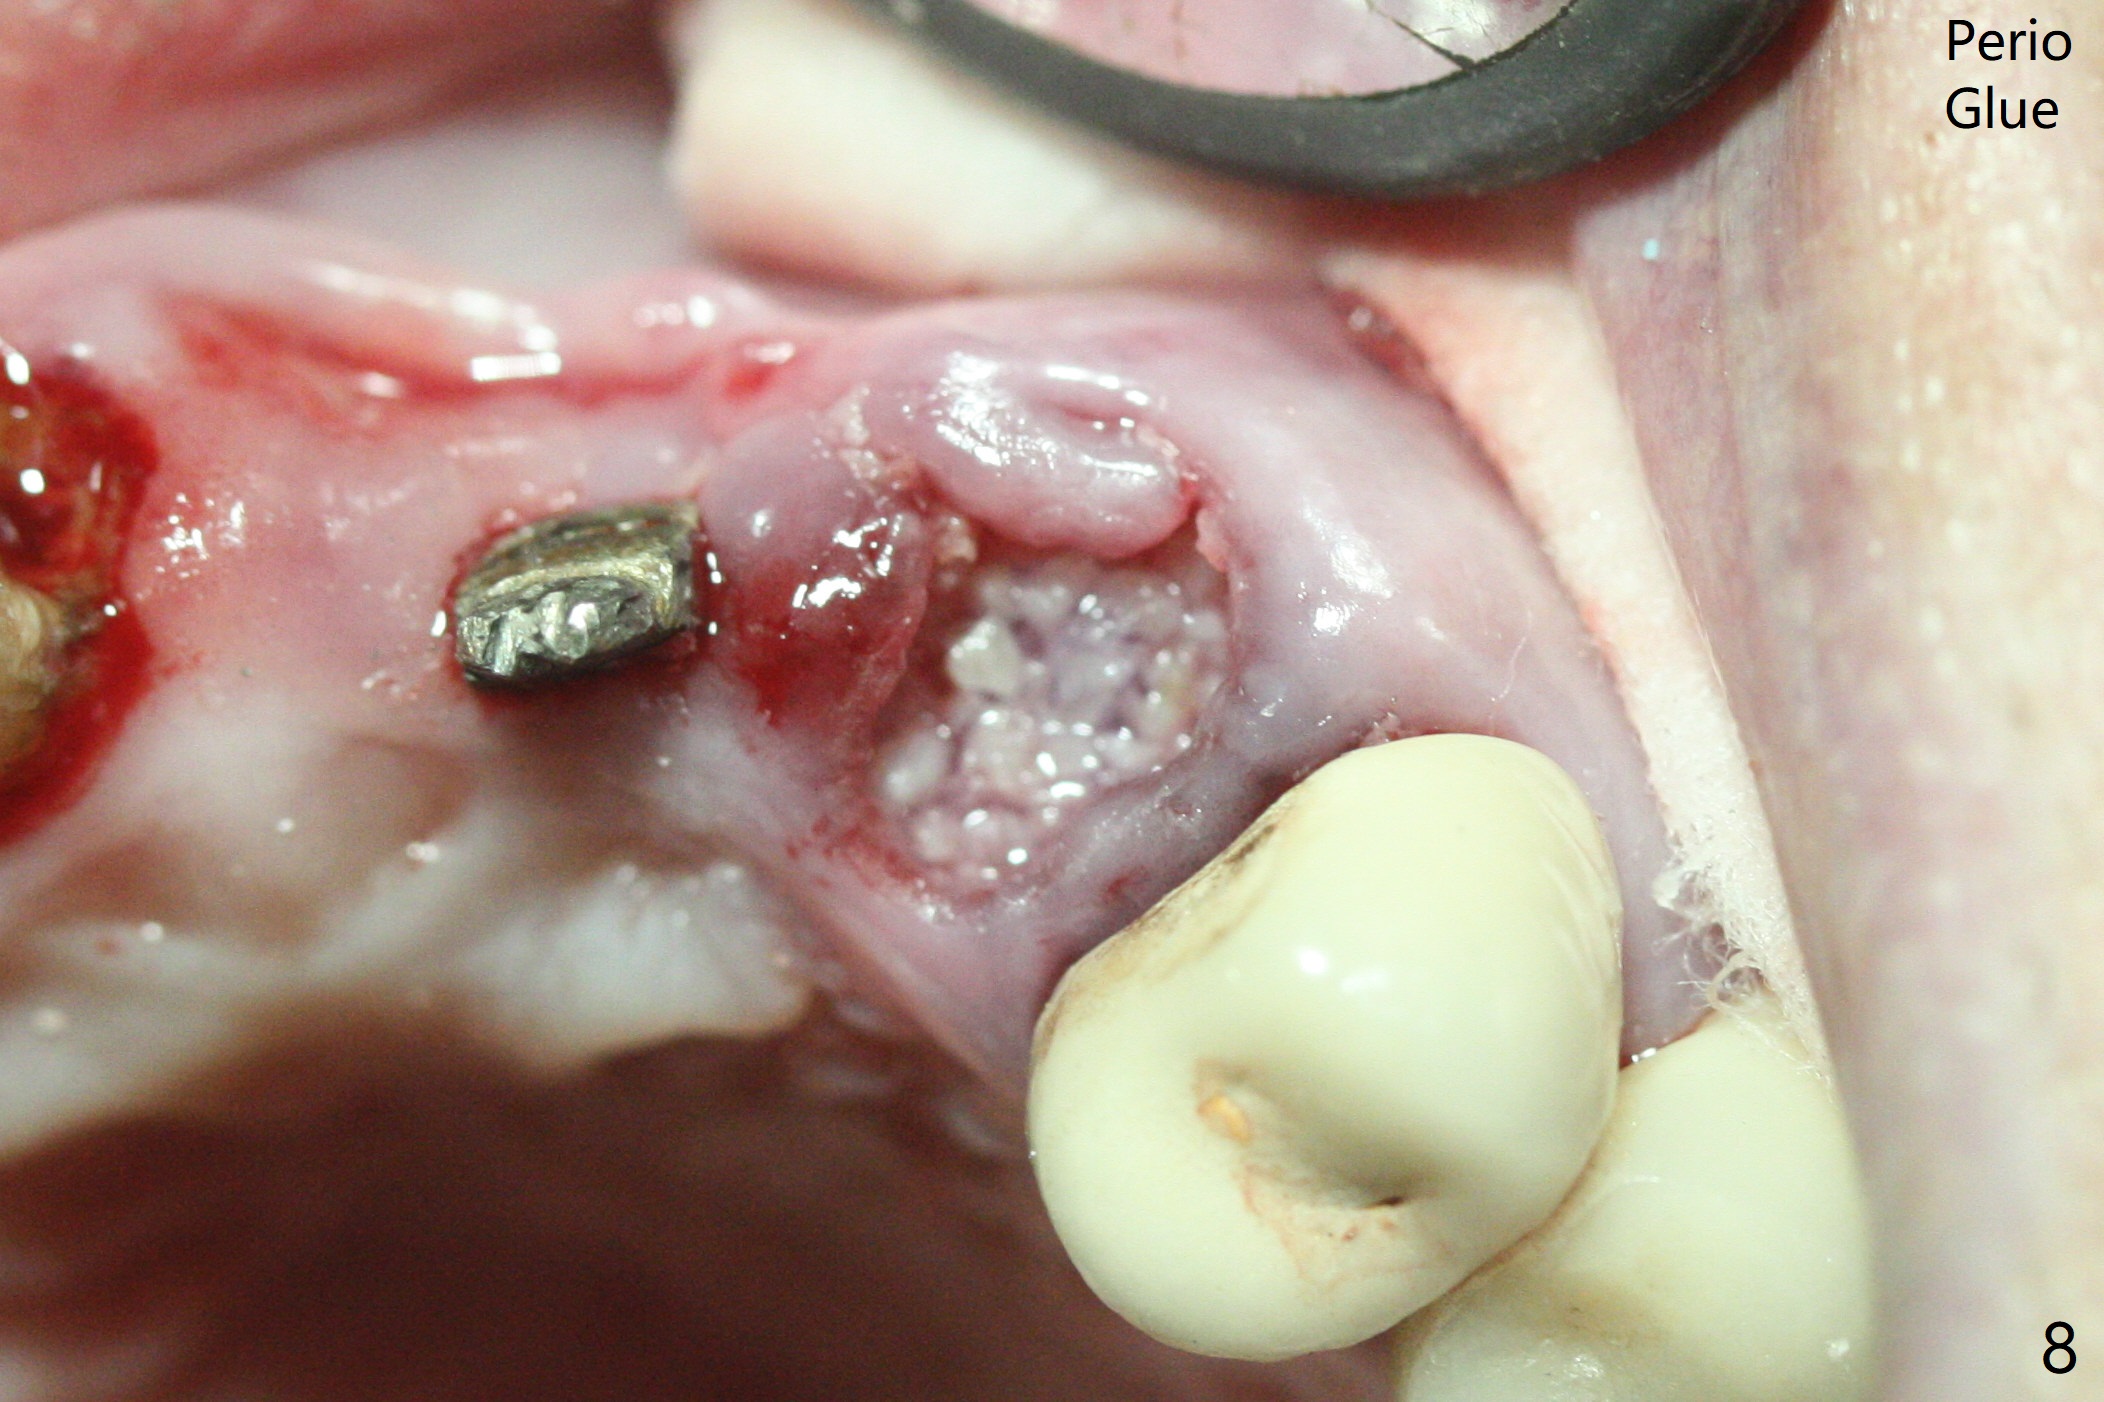

上前牙桥撤除显示右上1,2牙齿以及左上2叶片状植体好像可以保留,而左上3牙齿不能(图一,二(<:托牙边缘压迹)),拔除左上3牙齿后, 暂时把牙桥回位(图三:FPD(已经去除左上3号牙牙冠))作为3号牙种植位置参考(图四至六(G:骨粉))。其实植入前,当最后一个钻头还在原位,将PRF膜和粘性骨放置颊侧根尖(但愿骨粉能放深点),因为那里骨质很薄,好像缺损。由于植体扭力很低(大约5Ncm),放置骨粉覆盖植体(图七),为了不用缝线,涂牙周胶水(图八),放置胶原膜(图九),再涂胶水(图十)固定,最后利用右上1,2号牙(去龋,build-up后)和左上2植体制作临时牙桥,并且覆盖左上3牙槽窝。术后即刻CT显示植体颊侧(B)骨粉(图十一:*)。<:植体根尖仍有间隙,植体应该再长2毫米,初步稳定性会好些。左上3植牙愈合后,将与左上2植体制作左上1-3悬臂桥,右上1,2号牙将做根管治疗,桩,牙冠。临时牙桥术后十一天松动,右上一,二牙牙髓活性测定正常,深洗后,再次build up,不小心把左上3胶原膜吹掉,下面骨粉还稳定。术后三周病人回来做右上六种植,前牙临时修复体(图十二)需要修改(图十三)。拍摄三个方向照片显示前牙牙龈乳头(颊侧和咬合面)。